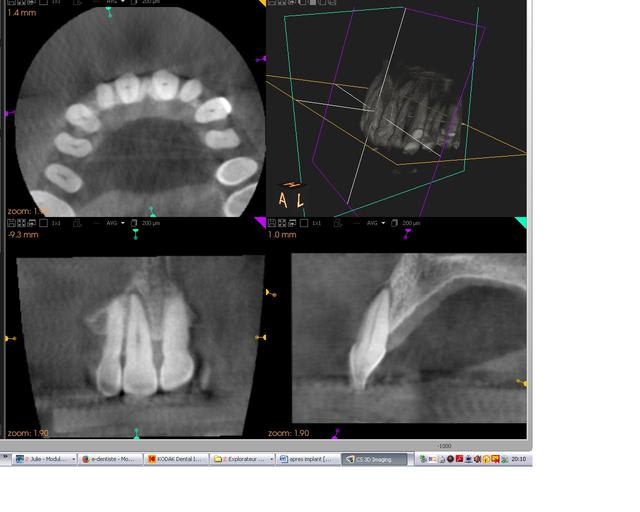

pour finir vous avez la 3D post op

3dpostop tkiukd - Eugenol